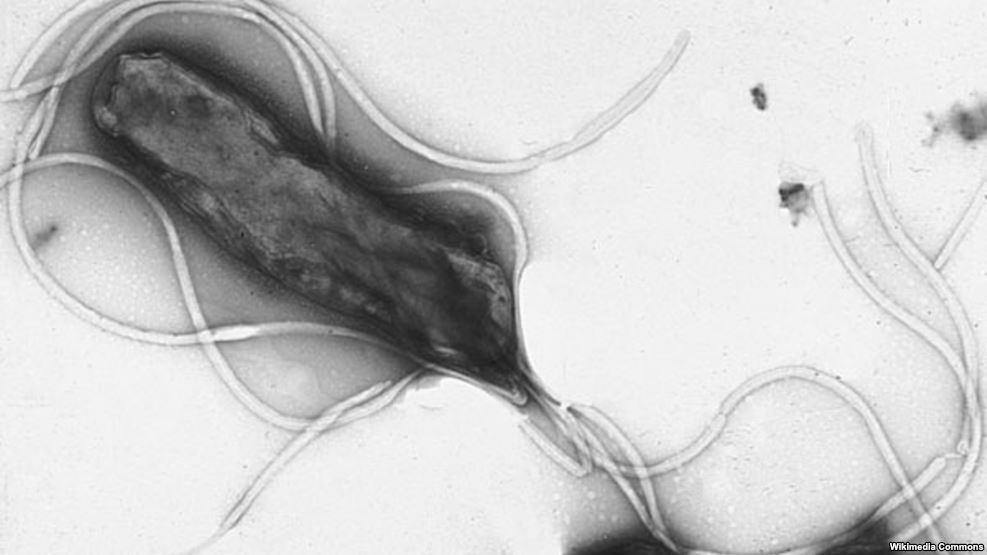

Среди белорусов вдвое больше носителей бактерии хеликобактер, чем среди жителей Евросоюза

Эта бактерия считается основным фактором гастрита и язвы желудка.

Хеликобактер может вызвать хронический гастрит, переходящий в язву желудка и двенадцатиперстной кишки, а также повышает риск развития рака желудка. «Хеликобактер рассматривается как точно установленный фактор развития рака желудка, а по распространенности этого заболевания Беларусь занимает одно из первых мест в Европе», — отметила Гаргун.